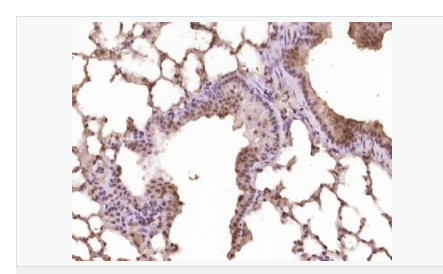

| 產(chǎn)品應(yīng)用 | WB=1:500-2000 ELISA=1:5000-10000 IHC-P=1:100-500 IHC-F=1:100-500 Flow-Cyt=1ug/Test ICC=1:100-500 IF=1:100-500 (石蠟切片需做抗原修復) not yet tested in other applications. optimal dilutions/concentrations should be determined by the end user. |

| 細胞定位 | 細胞核 |

| 產(chǎn)品介紹 | This gene encodes a member of the Notch family. Members of this Type 1 transmembrane protein family share structural characteristics including an extracellular domain consisting of multiple epidermal growth factor-like (EGF) repeats, and an intracellular domain consisting of multiple, different domain types. Notch family members play a role in a variety of developmental processes by controlling cell fate decisions. The Notch signaling network is an evolutionarily conserved intercellular signaling pathway which regulates interactions between physically adjacent cells. In Drosophilia, notch interaction with its cell-bound ligands (delta, serrate) establishes an intercellular signaling pathway that plays a key role in development. Homologues of the notch-ligands have also been identified in human, but precise interactions between these ligands and the human notch homologues remain to be determined. This protein is cleaved in the trans-Golgi network, and presented on the cell surface as a heterodimer. This protein functions as a receptor for membrane bound ligands, and may play multiple roles during development. [provided by RefSeq, Jul 2008]. Function: Notch family members play a role in a variety of developmental processes by controlling cell fate decisions. The Notch signaling network is an evolutionarily conserved intercellular signaling pathway which regulates interactions between physically adjacent cells. The protein is cleaved in the trans-Golgi network, and presented on the cell surface as a heterodimer. This protein functions as a receptor for membrane bound ligands. Once the Notch extracellular domain interacts with a ligand, a protease called TACE (Tumor Necrosis Factor Alpha Converting Enzyme) cleaves the Notch protein just outside the membrane. This releases the extracellular portion of Notch, which continues to interact with the ligand. The ligand plus the Notch extracellular domain is then endocytosed by the ligand expressing cell. After this first cleavage, an enzyme called gamma-secretase cleaves the remaining part of the Notch protein just inside the inner leaflet of the cell membrane. This releases the intracellular portion of the Notch protein, which then moves to the nucleus and causes various genes to be expressed. There are many other proteins involved in the intracellular portion of the Notch signalling cascade. Subunit: Heterodimer of a C-terminal fragment N(TM) and an N-terminal fragment N(EC) which are probably linked by disulfide bonds. Interacts with DNER, DTX1, DTX2 and RBPJ/RBPSUH. Also interacts with MAML1, MAML2 and MAML3 which act as transcriptional coactivators for NOTCH1. The activated membrane-bound form interacts with AAK1 which promotes NOTCH1 stabilization. Forms a trimeric complex with FBXW7 and SGK1. Interacts with HIF1AN. HIF1AN negatively regulates the function of notch intracellular domain (NICD), accelerating myogenic differentiation. Subcellular Location: Cell membrane; Single-pass type I membrane protein. Notch 1 intracellular domain: Nucleus. Note=Following proteolytical processing NICD is translocated to the nucleus. Tissue Specificity: In fetal tissues most abundant in spleen, brain stem and lung. Also present in most adult tissues where it is found mainly in lymphoid tissues. Post-translational modifications: Synthesized in the endoplasmic reticulum as an inactive form which is proteolytically cleaved by a furin-like convertase in the trans-Golgi network before it reaches the plasma membrane to yield an active, ligand-accessible form. Cleavage results in a C-terminal fragment N(TM) and a N-terminal fragment N(EC). Following ligand binding, it is cleaved by TNF-alpha converting enzyme (TACE) to yield a membrane-associated intermediate fragment called notch extracellular truncation (NEXT). Following endocytosis, this fragment is then cleaved by presenilin dependent gamma-secretase to release a notch-derived peptide containing the intracellular domain (NICD) from the membrane (By similarity). Phosphorylated (By similarity). O-glycosylated on the EGF-like domains. Contains both O-linked fucose and O-linked glucose. Ubiquitinated; undergoes 'Lys-29'-linked polyubiquitination catalyzed by ITCH. Monoubiquitination at Lys-1759 is required for activation by gamma-secretase cleavage, it promotes interaction with AAK1, which stabilizes it. Deubiquitination by EIF3F is necessary for nuclear import of activated Notch. Hydroxylated at Asn-1955 by HIF1AN. Hydroxylated at Asn-2022 by HIF1AN (By similarity). Hydroxylation reduces affinity for HI1AN and may thus indirectly modulate negative regulation of NICD. DISEASE: Defects in NOTCH1 are a cause of aortic valve disease 1 (AOVD1) [MIM:109730]. A common defect in the aortic valve in which two rather than three leaflets are present. It is often associated with aortic valve calcification and insufficiency. In extreme cases, the blood flow may be so restricted that the left ventricle fails to grow, resulting in hypoplastic left heart syndrome. Similarity: Belongs to the NOTCH family. Contains 5 ANK repeats. Contains 36 EGF-like domains. Contains 3 LNR (Lin/Notch) repeats. SWISS: P46531 Gene ID: 4851 Database links: Entrez Gene: 4851 Human Entrez Gene: 18128 Mouse Omim: 190198 Human SwissProt: P46531 Human SwissProt: Q01705 Mouse Unigene: 495473 Human nigene: 290610 Mouse Important Note: This product as supplied is intended for research use only, not for use in human, therapeutic or diagnostic applications. |